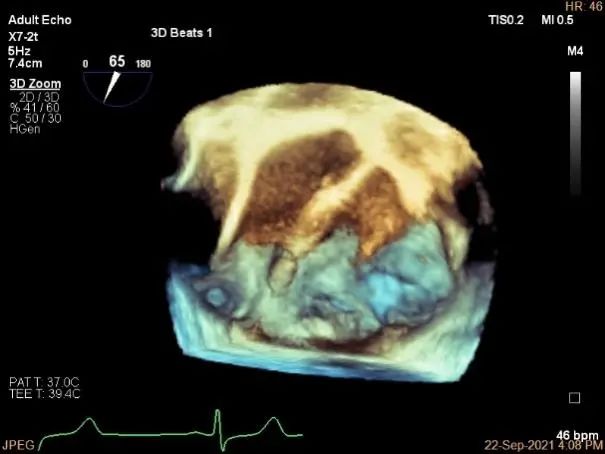

术中超声

P2区脱垂,宽14.8mm,Gap:3.3mm

3D-color,返流重度,3+级

三维评估两个夹子位置

3D-color再次确定未见残余分流